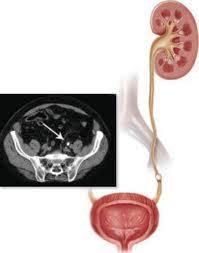

Камень в мочеточнике

камень мочеточника - рисунокИсходя из своего происхождения камни мочеточника подразделяются на первичные (образовались в пределах мочеточника), и вторичные (образовались в почке и мигрировали в мочеточник). Сразу следует сказать о том, что первичные конкременты М-ка встречаются крайне редко (например, камень дивертикула мочеточника).

Диагностика основывается на данных клинической картины, осмотра, пальпации. Пальпация почек болезненна, симптом поколачивания – резко-положительный. В период, когда почечная колика по тем или иным причинам купировалась, может отмечаться болезненность при пальпации в трех точках Турне: точки анатомических сужений мочеточника. Для уточнения диагноза применяется УЗИ почек, верхней и нижней трети мочеточника, экскреторная урография, компьютерная томография.